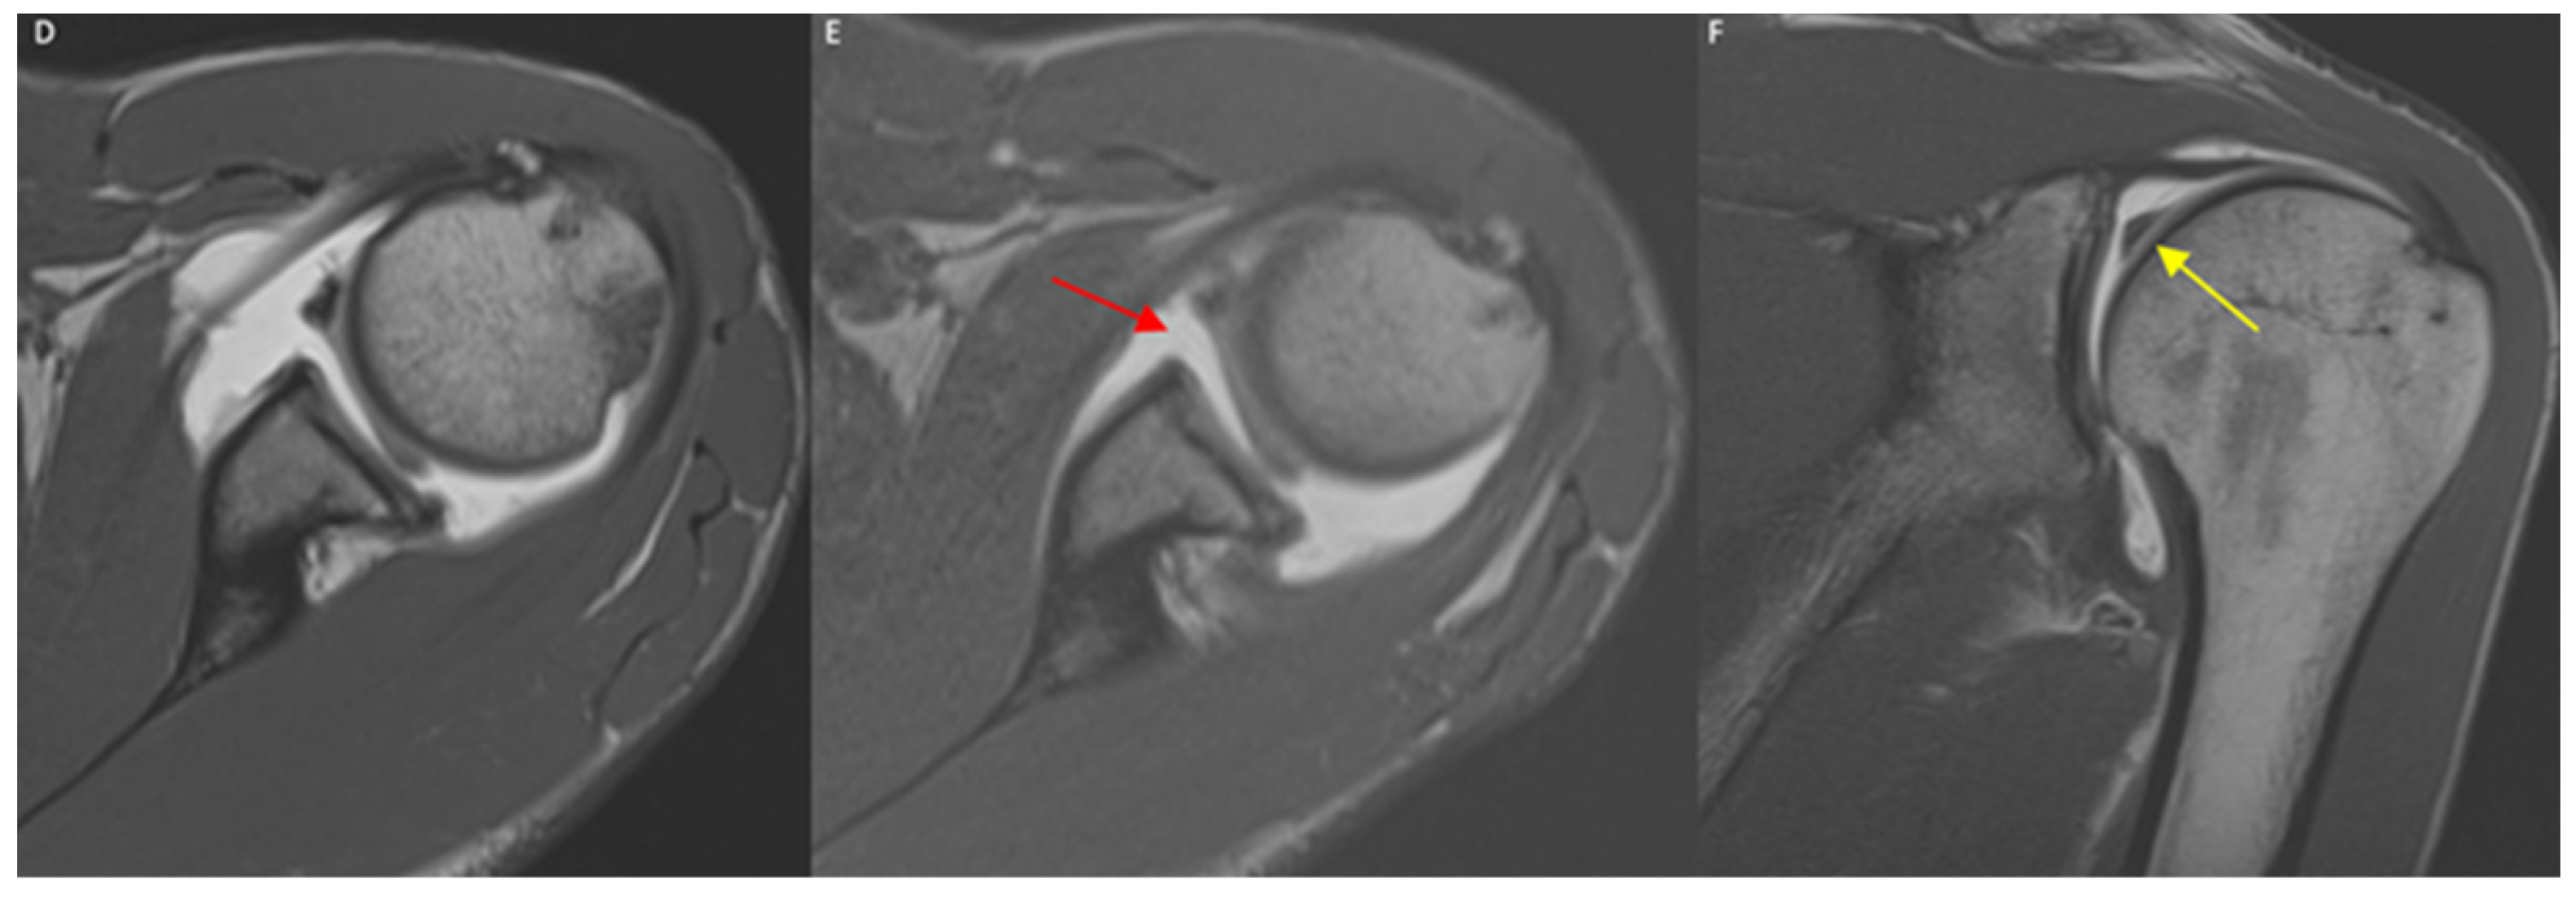

Rater 1’s diagnosis based on the MRA acquired in the ER or N positions differed in 19/130 cases (14.6%). In all such cases, the diagnosis was negative based on the MRA acquired in the N position but positive based on the images acquired in the ER position (Figure 6).

Figure 6.

(A–C) A 45-year-old male, axial T1-weighted images in IR (A), N (B), and ER (C) positions: only in the ER scan can a SLAP lesion be detected as a linear hyperintense contrast media infiltration within the bicipital–labrum complex (yellow arrow), representing a type II SLAP lesion. *: long head of the biceps tendon; (D–F) a 37-year-old male, axial T1-weighted images in N (D) and ER (E) positions, and coronal T1-w image in N position (F): a SLAP lesion is clear also in N standard position, but the ER of the humeral head increases the diastasis of the lesion (red arrow). Coronal image well demonstrates a bucket-handle tear of superior labrum (yellow arrow) with biceps tendon correctly attached to glenoid, expression of a type III SLAP lesion.